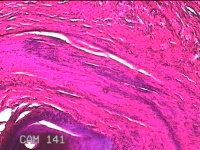

肛周结节

性别

男

年龄

43岁

临床诊断

外痔

一般病史

发现肛周结节,伴疼痛不适1年余,考虑息肉状外痔。

标本名称

大体所见

灰白暗红色结节0.8x0.7x0.3cm一个,表面糜烂,切面灰白暗红色,质软。